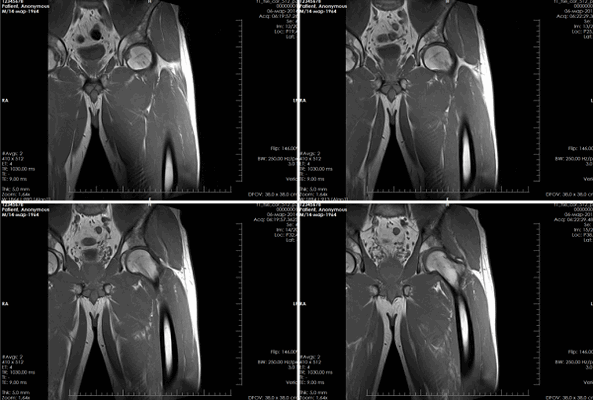

(Слева) МРТ после переднебокового вывиха коленного сустава и закрытой репозиции, PDBИ, режим подавления сигнала от жира, сагиттальный срез: определяется разрыв ПКС. На задней поверхности большеберцовой кости определяется небольшой отек костного мозга.

(Справа) МРТ PDBИ, режим подавления сигнала от жира, сагиттальный срез, медиальнее предыдущею изображения: у этою же пациента определяется разрыв ЗКС более дистально. Обе крестовидные связки разрывают в большинстве вывихов колена. (Слева) МРТ Т2ВИ, режим подавления сигнала от жира, коронарный срез: у этою же пациента определяется дистальный отрыв МКС с окружающим оторванную связку скоплением жидкости. Разрыв ПКС визуализируется в виде аморфного серого сигнала в межмыщелковой вырезке. МБКС не повреждена.

(Справа) МРТ PDBИ, сагиттальный срез: определяется полный передний вывих большеберцовой кости по отношению к бедренной кости. Разорванная ЗКС четко визуализируется. Латеральная поверхность механизма разгибания не повреждена. (Слева) МРТ после переднею вывиха колена, Т2ВИ, режим подавления сигнала от жира, коронарный срез: определяется разрыв МБКС с формированием гематомы вокруг мягкотканных структур. Межмыщелковая вырезка заполнена аморфным серым сигналом вследствие разрыва обеих ИКС и ЗКС. Определяются вколоченные ушибы в медиальном мыщелке бедренной кости и медиальной поверхности большеберцовой кости. МКС не повреждена.

(Справа) МРТ PDBИ, режим подавления сигнала от жира, аксиальный срез: у этою же пациента определяется разрыв МБКС, ПКС и ЗКС.